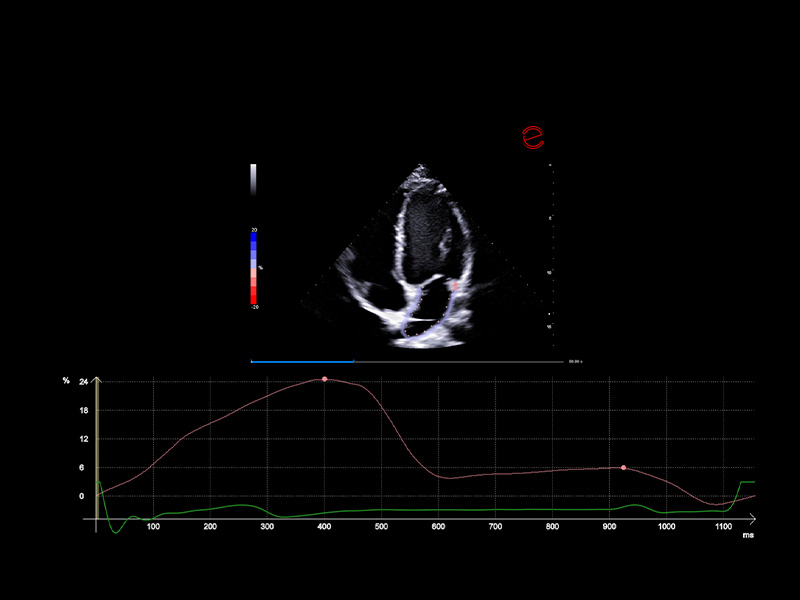

Advanced myocardial strain analysis with XStrain™

Esaote’s XStrain™ technology offers cutting-edge myocardial deformation analysis across multiple cardiac chambers and views—including the left ventricle (LV), right ventricle (RV), left atrium (LA), and short-axis (SAX) planes. Utilizing speckle-tracking algorithms, XStrain™ provides a detailed evaluation of the global and segmental strain, enabling early detection of subtle systolic dysfunction that is often missed by traditional metrics.

XStrain™ delivers precise global longitudinal strain (GLS) measurements with intuitive visual reports, including bull’s-eye maps and strain curves. This comprehensive assessment aids clinicians in diagnosing cardiomyopathies, chemotherapy-induced cardiotoxicity, and complex structural heart diseases with great confidence, allowing for earlier intervention and improved patient outcomes.